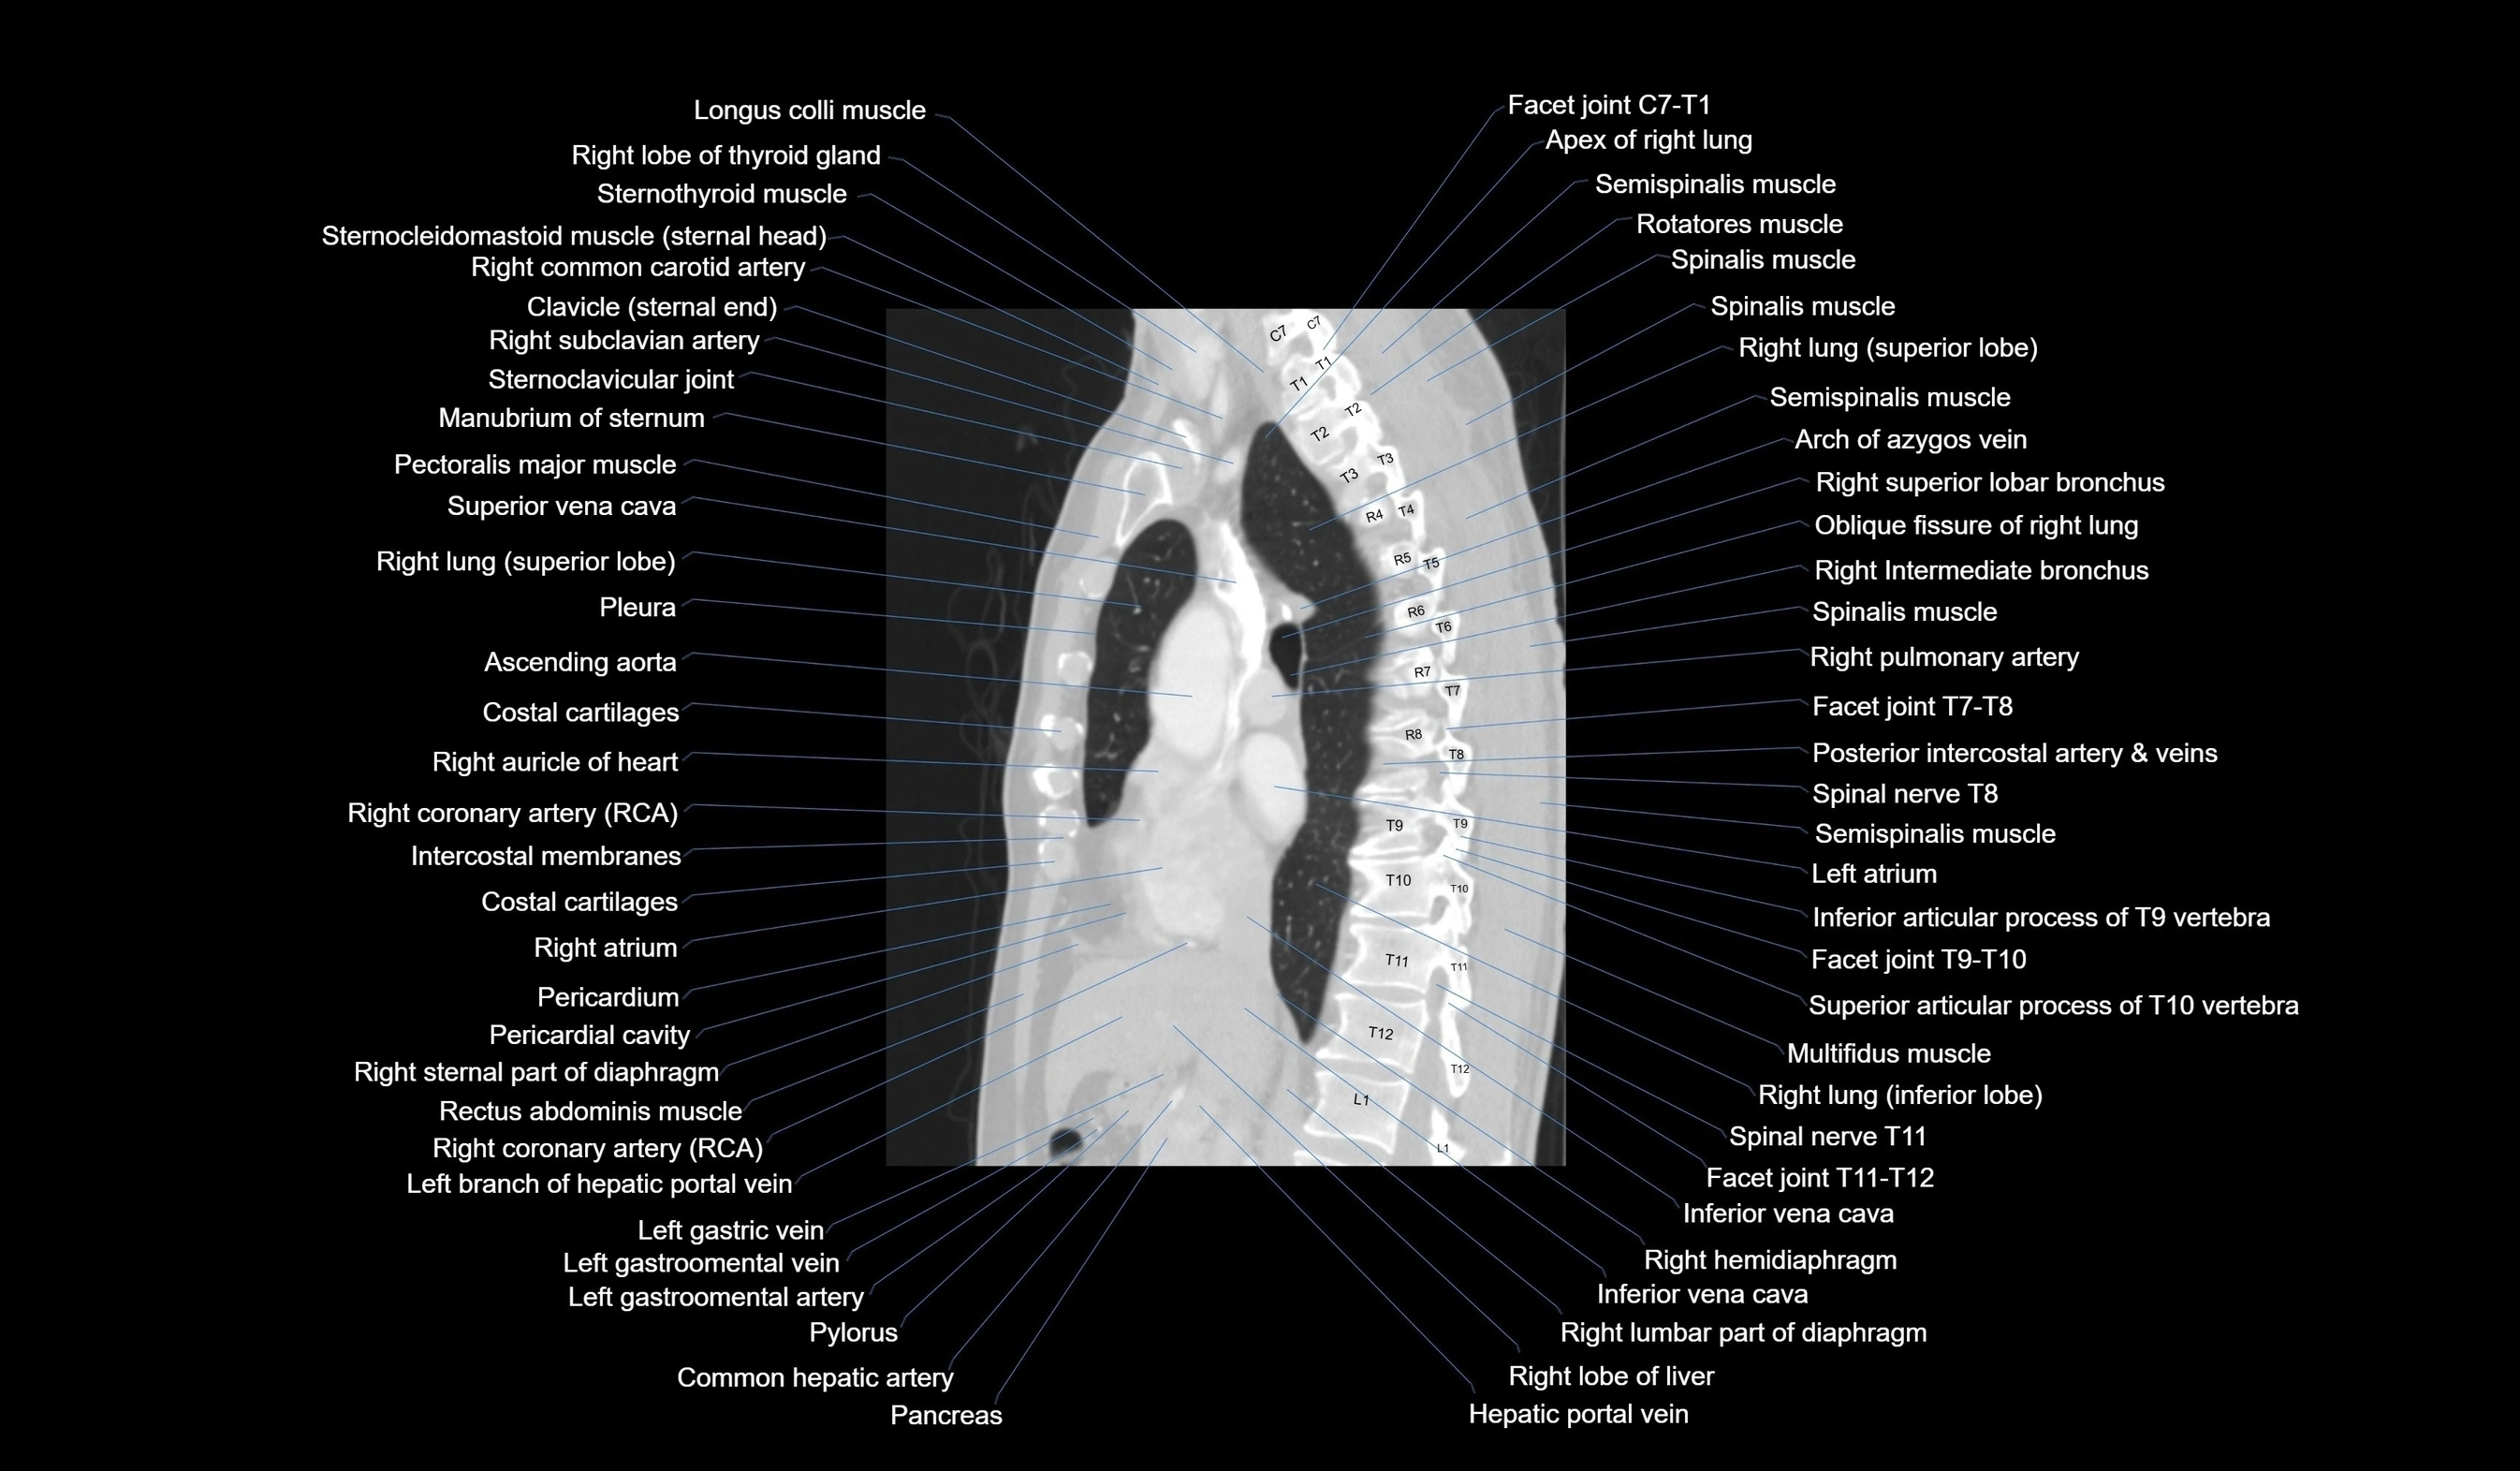

- T (Thoracic spine)

- Apex of right lung

- Right lung (superior lobe)

- Right lung (inferior lobe)

- Oblique fissure of right lung

- Azygos vein

- Right superior lobar bronchus

- Right intermediate bronchus

- Right pulmonary artery

- Right coronary artery (RCA)

- Right atrium

- Ascending aorta

- Descending thoracic aorta

- Inferior vena cava

- Hepatic portal vein

- Pancreas

- Common hepatic artery